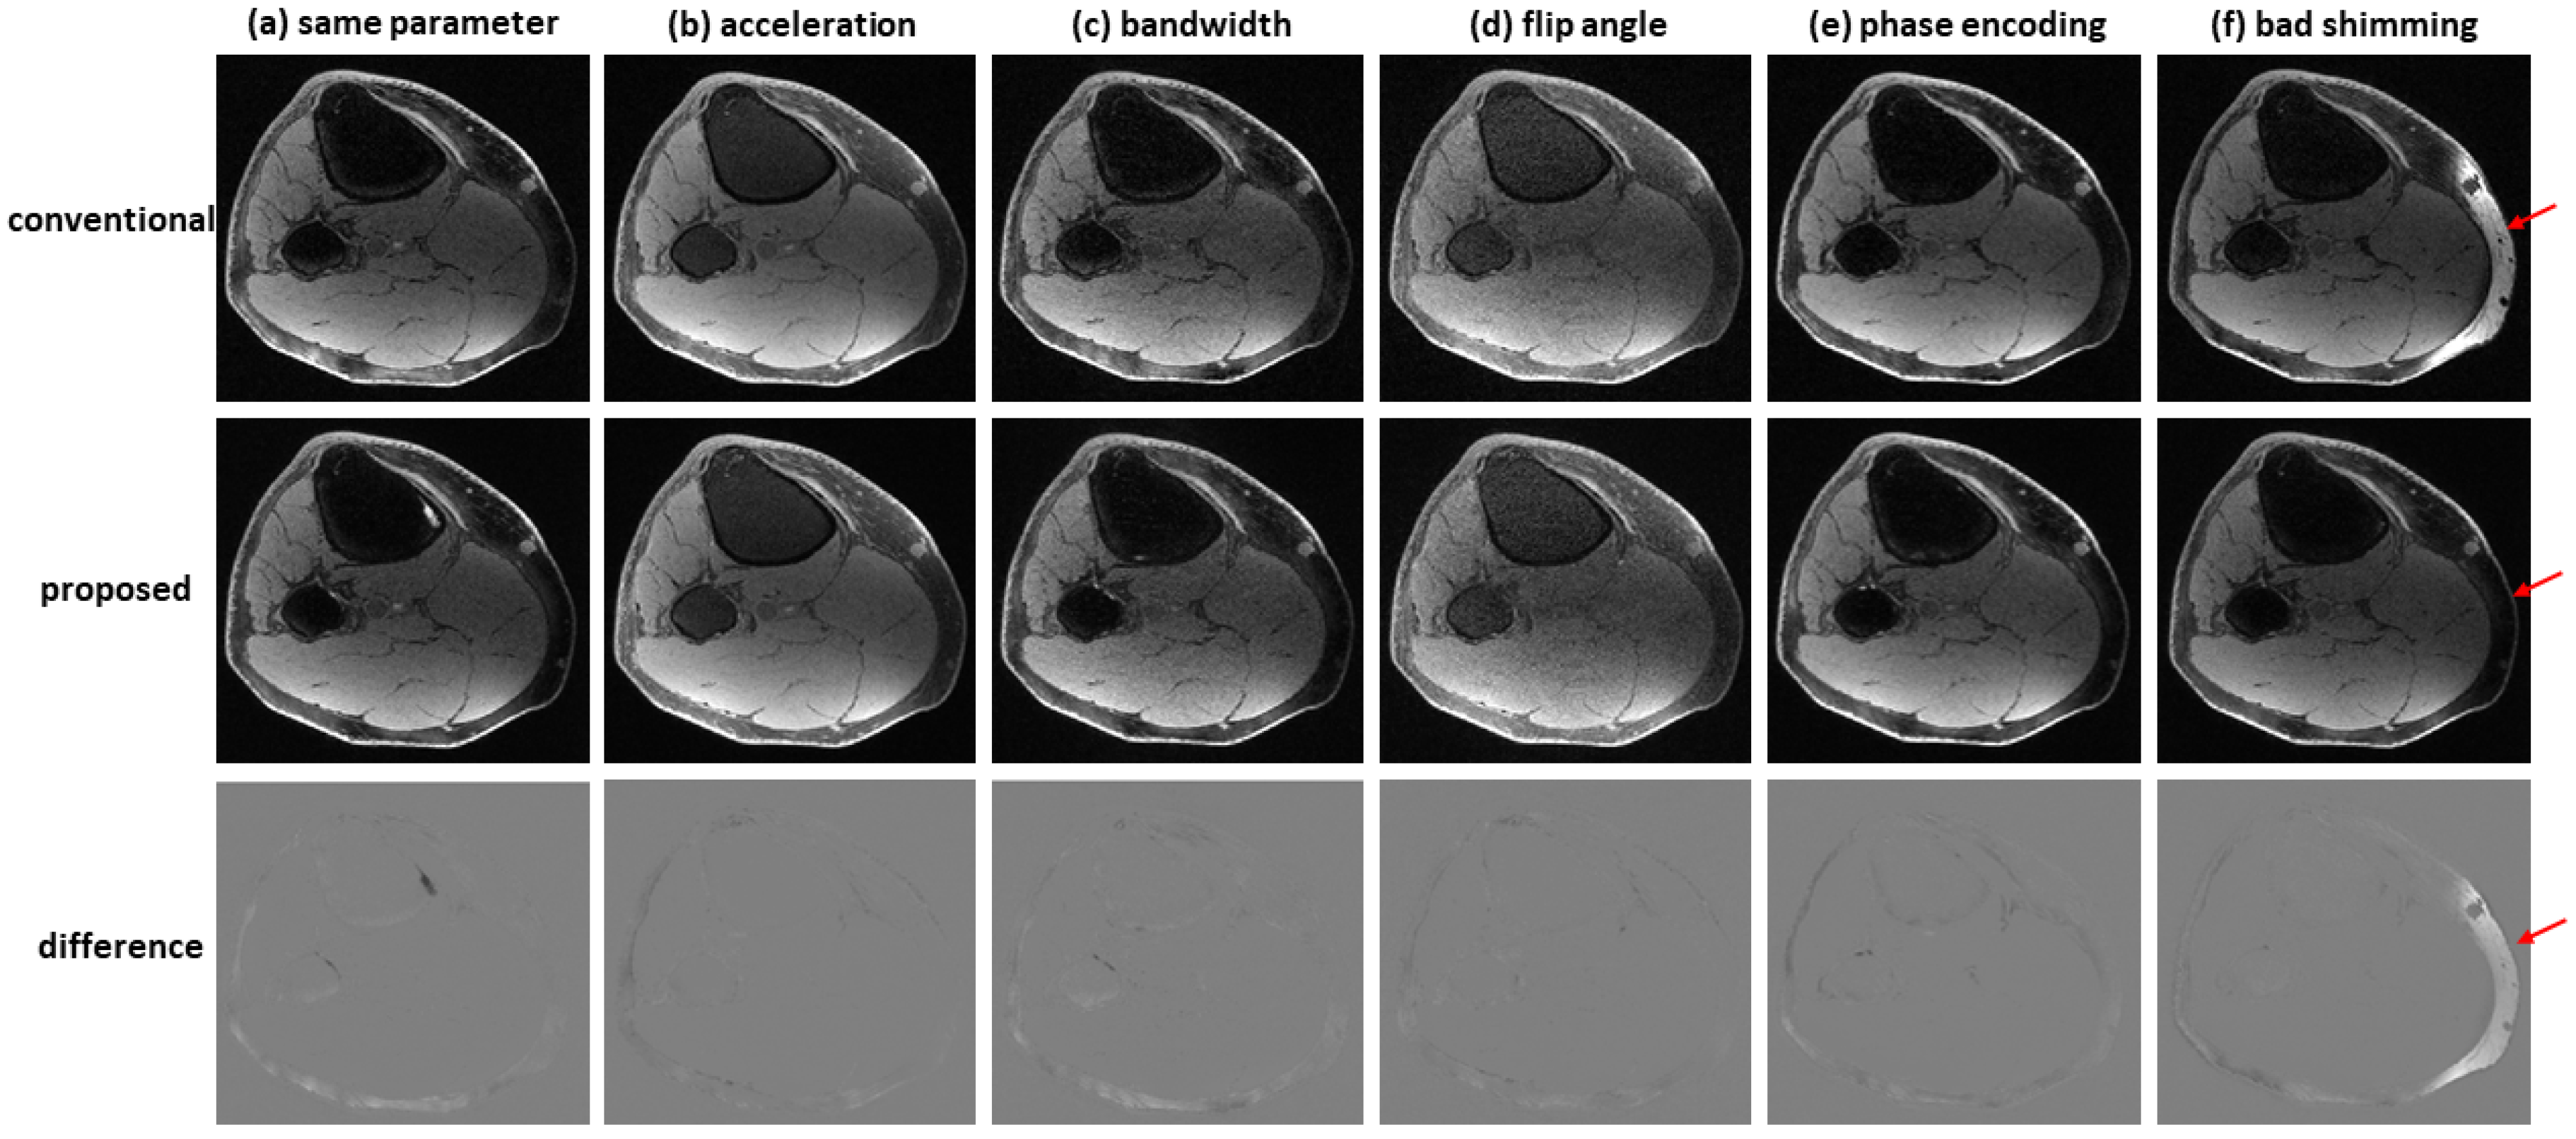

Figure 7 shows an example of water–fat separation from non-contrast-enhanced dual-echo images using a model trained with contrast-enhanced images. Even if the imaging parameters were slightly different from those adopted in contrast-enhanced studies (with an acceleration factor of 2, bandwidth of 83.3 kHz, flip angle of 25°, or phase encoding of 224), the predicted images had high fidelity to the reference images, indicating the proposed method has high potential to support flexible imaging parameters. When bad shimming was intentionally imposed (to generate highly inhomogeneous B 0 field), water/fat swaps that occurred in reference images were corrected in the predicted images.

Figure 7. Water–fat separation from non-contrast-enhanced dual-echo images using a model trained with contrast-enhanced images. The non-contrast-enhanced dual-echo images were acquired using (a) the same imaging parameters as those adopted in contrast-enhanced studies, (b) an acceleration factor of 2, (c) bandwidth of 83.3 kHz, (d) flip angle of 25°, and (e) phase encoding of 224. In these cases, the predicted images had high fidelity to the reference images. (f) When bad shimming was intentionally imposed, water/fat swaps that occurred in the reference image were corrected in the predicted image.